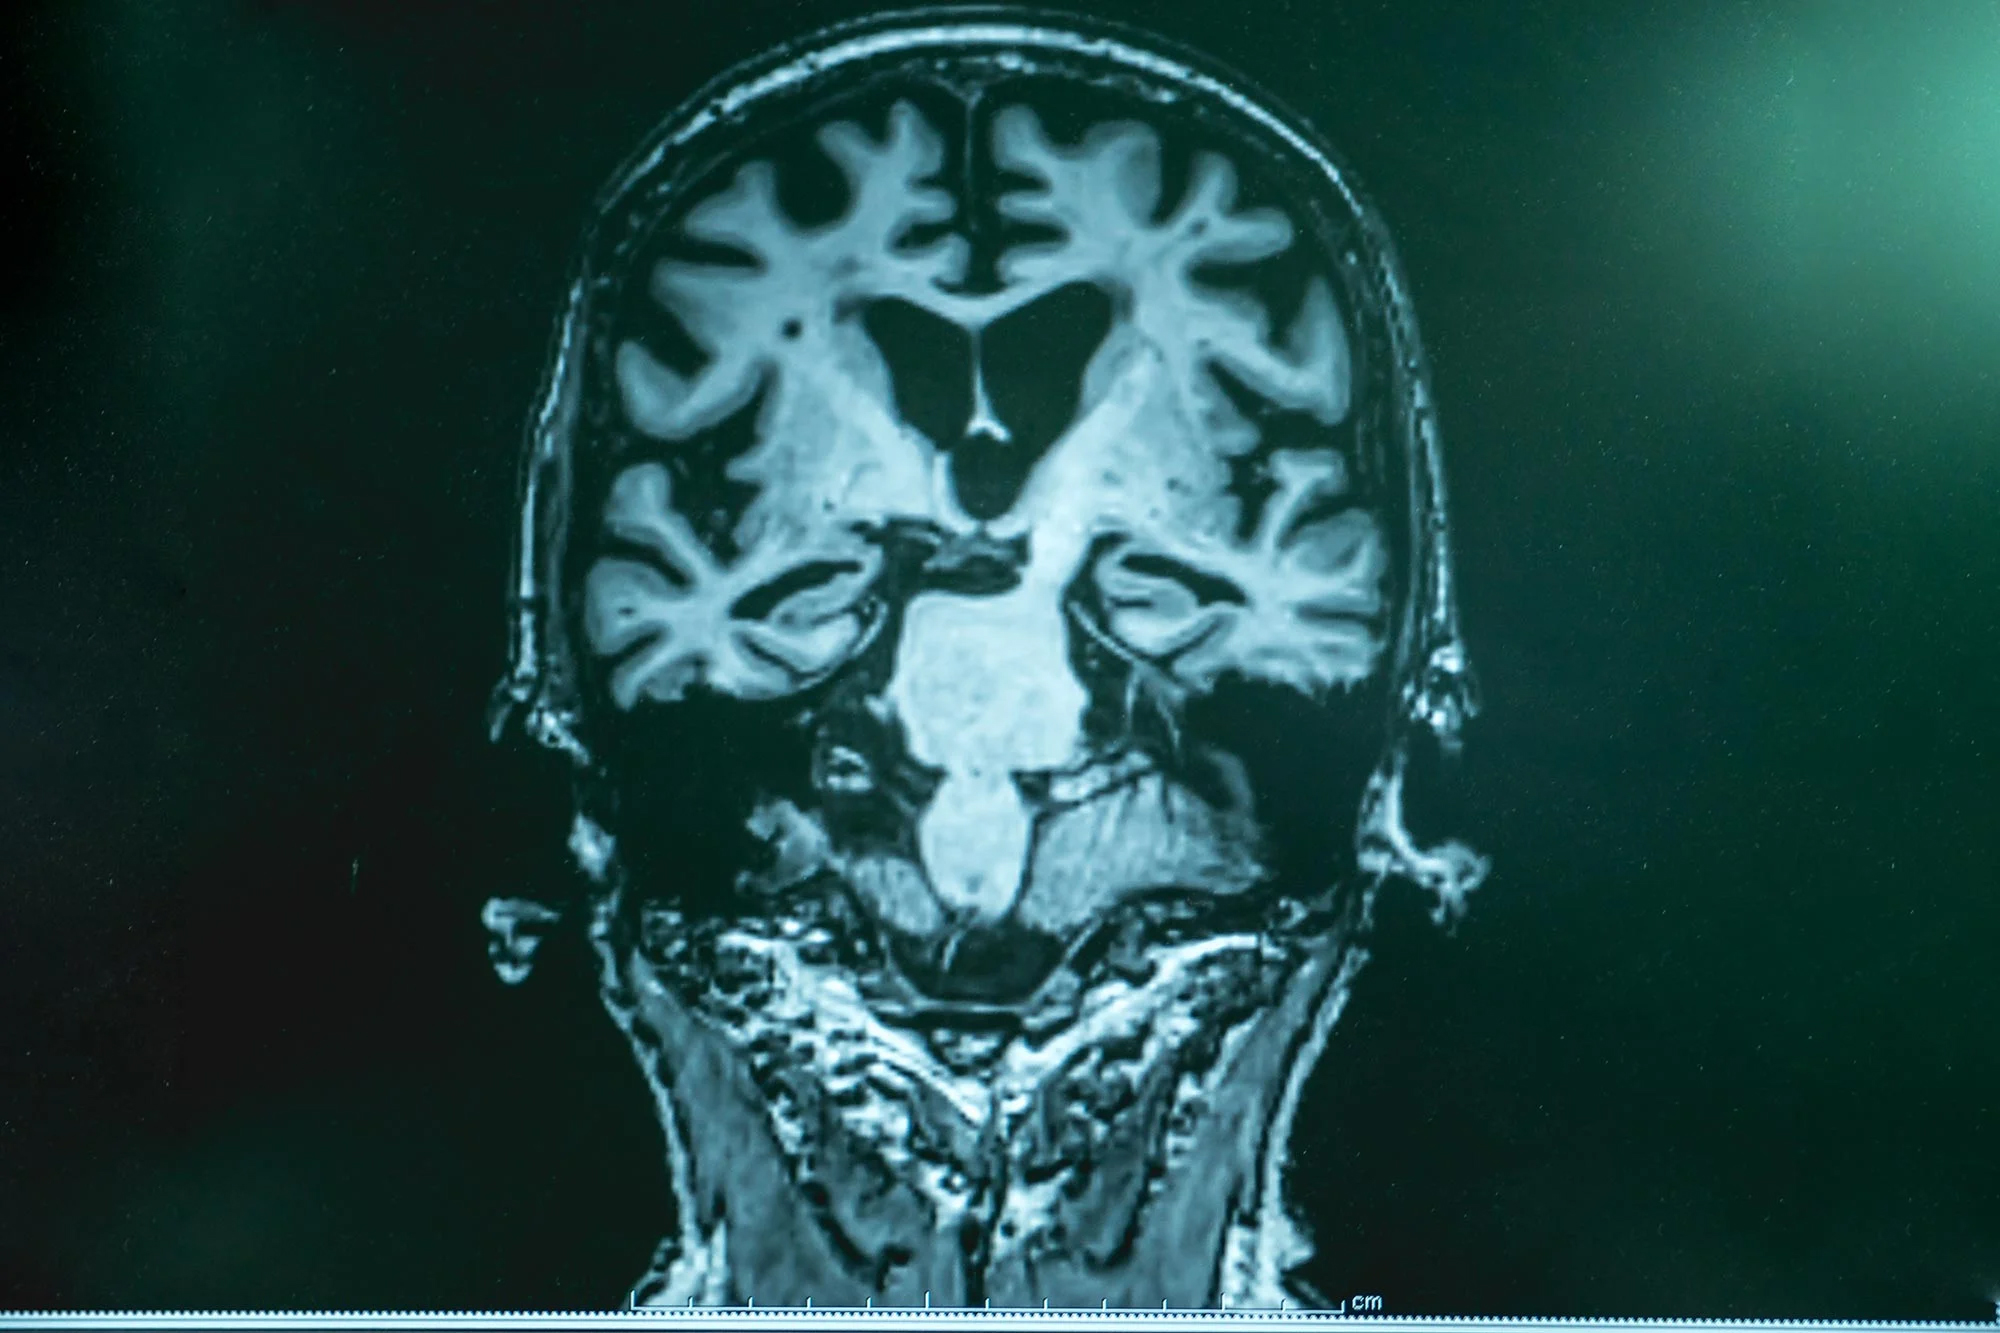

تقویت ریپلهای خواب حافظههای فراموششده را حفظ میکند

دستکاری مغز موشها در هنگام خواب، توانایی آنها را برای بهخاطر سپردن تجربیات جدیدی که معمولاً فراموش میشوند، بهبود بخشید؛ یافتهای که پیامدهای مهمی برای درمان بیماری آلزایمر و سایر انواع زوال عقل دارد که ادامه مطلب

کلیدی که دفاع مغز را علیه آلزایمر بسیج میکند

سلولهای خاص ایمنی در مغز ممکن است نقش حیاتی در جلوگیری از بروز بیماری آلزایمر ایفا کنند؛ بر اساس یک مطالعه جدید، این کشف میتواند به توسعه درمانهایی منجر شود که تلاش میکنند این سلولها ادامه مطلب

آزمایش سه دقیقهای مغزی، آلزایمر را زود تشخیص میدهد

یک آزمایش ساده امواج مغزی که در دانشگاه باث توسعه یافته، نشان داده است میتواند نشانههای اختلال حافظه مرتبط با بیماری آلزایمر را سالها پیش از زمان تشخیص بالینی معمول شناسایی کند. مطالعهای که در ادامه مطلب